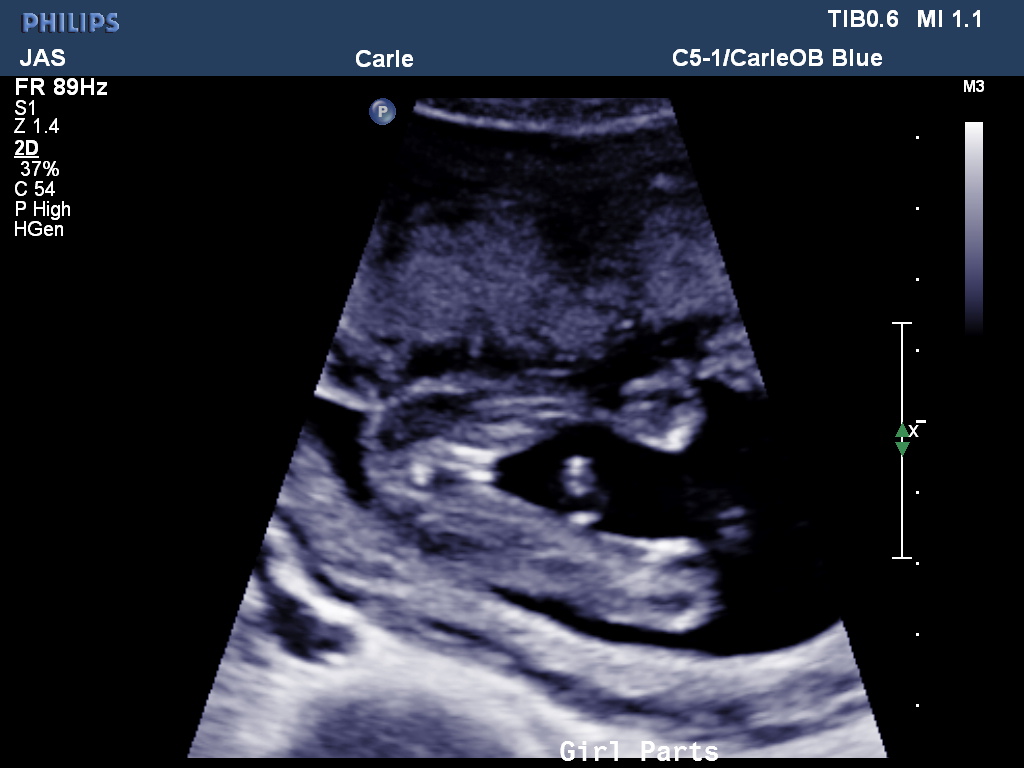

Holy cow, it’s hard to believe I’m writing this post already! I am already half way through my fourth pregnancy and so far I can’t complain. About two weeks ago we found out were are having another baby girl and are thrilled and really surprised (I had convinced myself AND Ty that we were having a boy!). She looked healthy and for that we are grateful! So far I’ve put on 6 lbs and for the most part I’m feeling great. However, the more little ones hanging on my legs and running around the house makes doing anything, especially pregnant, more difficult. I think I’m right on track to putting on my normal 35 and for looking like a torpedo belly (Thanks, Ty!). I am in the middle of looking for a new OB in Grand Rapids, but have no doubt I’ll find someone soon!

Here’s our baby girl: